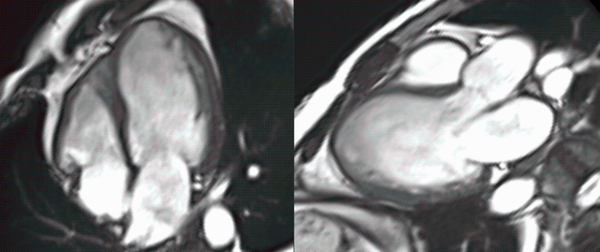

COD 077 - Decoding Septum Predominant Hypertrophic Cardiomyopathy

Understanding standard septum predominant HCM